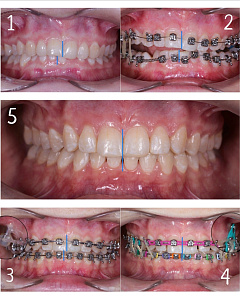

Гегиров Амир Артурович (@amir__ortodont)

Врач-ортодонт

#repost от @amir__ortodont

Была проведена полная фиксация брекетов на обе челюсти, установлены дуги и дополнительные элементы для запуска контролируемого перемещения зубов. Уже с первых месяцев лечения начинается работа над выравниванием зубных рядов, подготовкой места для правильного положения клыков и коррекцией прикуса.

В данном случае наблюдается выраженный дефицит места для клыков, поэтому лечение будет проходить поэтапно и с использованием дополнительной опоры. Каждый элемент системы работает на прогнозируемый и максимально эффективный результат.

Была проведена полная фиксация брекетов на обе челюсти, установлены дуги и дополнительные элементы для запуска контролируемого перемещения зубов. Уже с первых месяцев лечения начинается работа над выравниванием зубных рядов, подготовкой места для правильного положения клыков и коррекцией прикуса.

В данном случае наблюдается выраженный дефицит места для клыков, поэтому лечение будет проходить поэтапно и с использованием дополнительной опоры. Каждый элемент системы работает на прогнозируемый и максимально эффективный результат.